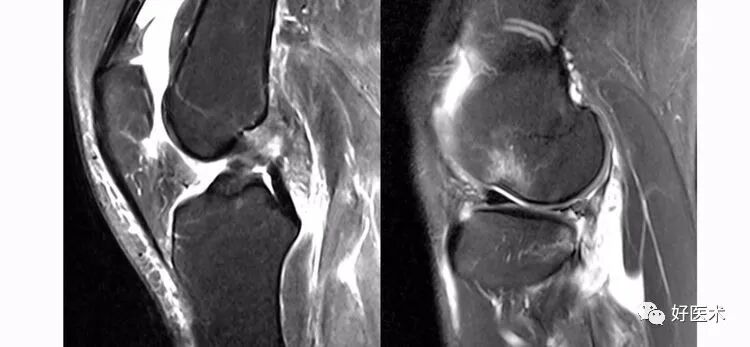

(二)ACL的正常MRI表现

-

各序列均为低信号。

韧带平直,边界清楚,有较好的张力。

韧带内可有脂肪及滑膜条纹影。

(三)ACL损伤的MRI分级

Grade1:韧带内损伤,无长度改变。

Grade2:韧带内损伤并长度延长。

Grade3:完全性韧带撕裂。

Grade1、2级是部分损伤。

Grade3级是完全损伤。